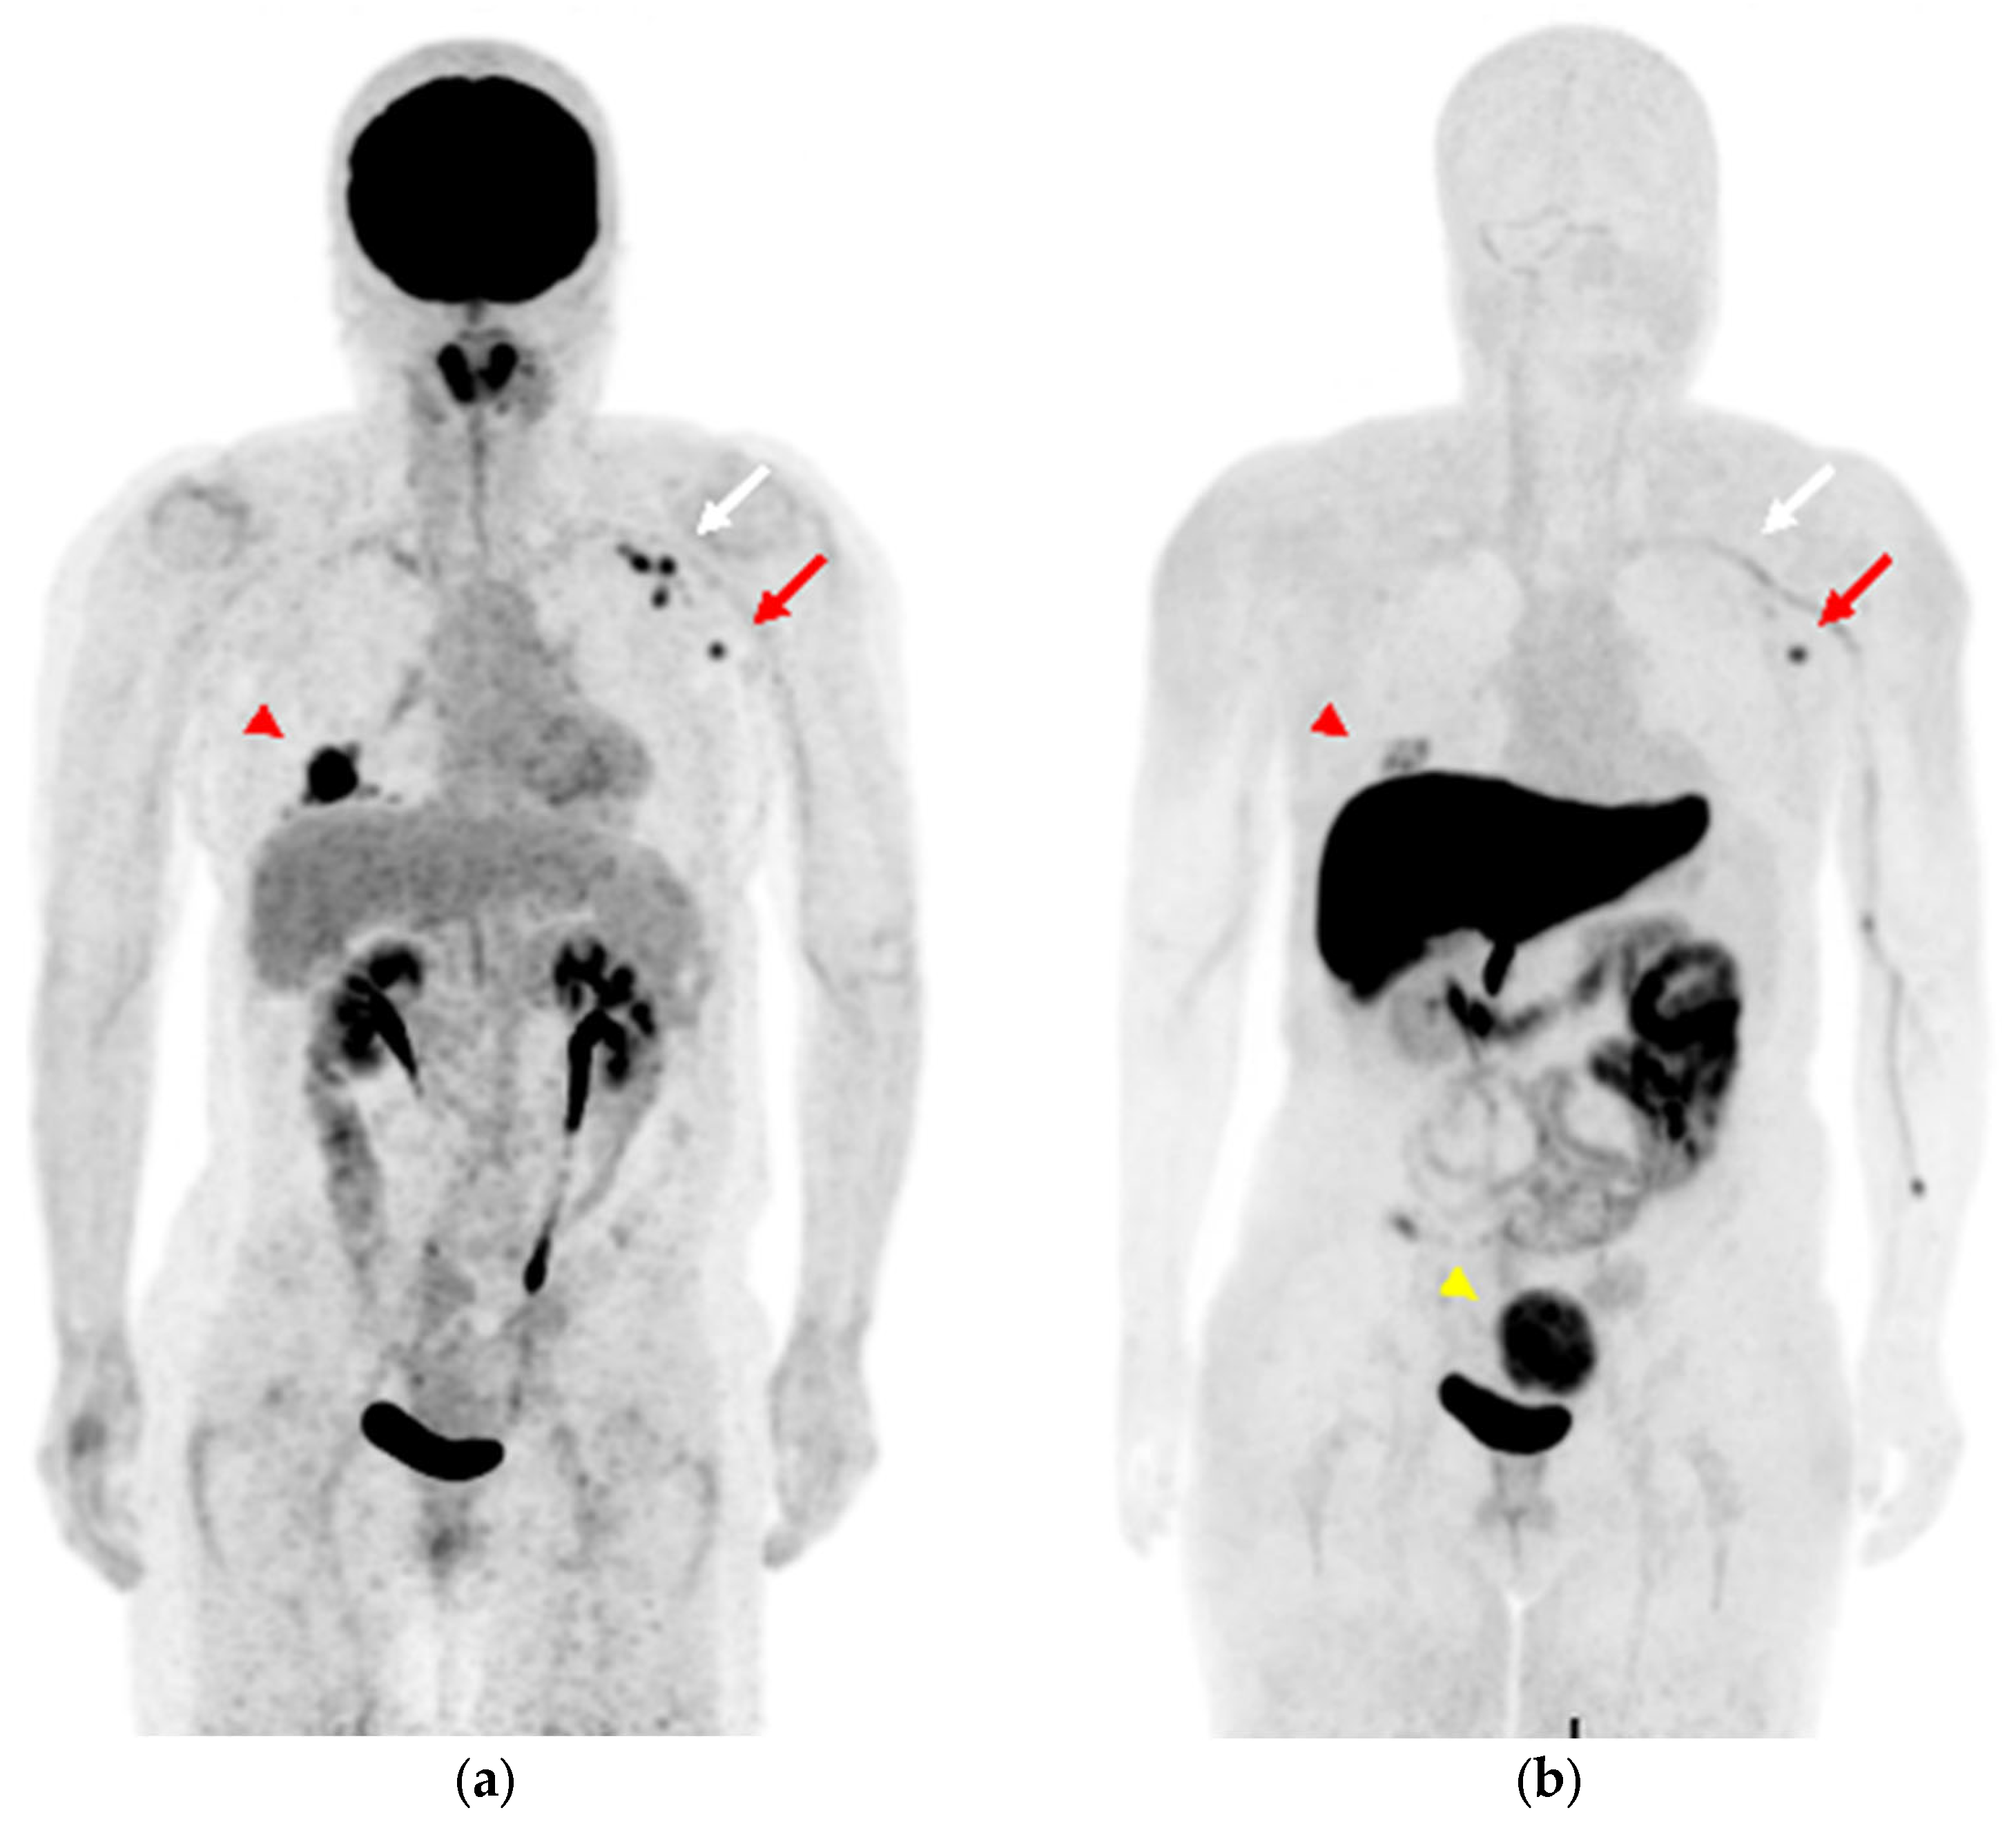

A 58-year-old woman was diagnosed with ER-positive right breast cancer on histopathological examination using H&E staining and IHC (ER 80%, PgR 80%, HER2 score1, MIB-1 index 10%). She underwent pretreatment [18F]FDG PET/CT for staging. In addition to intense [18F]FDG uptake in the primary breast tumor (Figure 4a and Figure 5a, red arrowhead), increased [18F]FDG uptake was observed in level I (Figure 4a and Figure 5b, red arrow) and level II contralateral axillary lymph nodes (Figure 4a and Figure 5c, white arrow). Since she was vaccinated against COVID-19 (the Moderna COVID-19 vaccine) in her left deltoid muscle 12 days before the [18F]FDG PET/CT scan, the [18F]FDG-avid contralateral axillary lymph nodes were considered as vaccine-associated hypermetabolic lymphadenopathy. She had undergone surgery for the right axillary ganglion, and we suspected possible altered lymphatic drainage. Four weeks after [18F]FDG PET/CT, she underwent [18F]FES PET/MRI to evaluate the ER expression of the lesions. [18F]FES PET/MRI showed moderate [18F]FES uptake in the ER-positive right breast cancer (Figure 4b and Figure 5d, red arrowhead) and high [18F]FES uptake in the level I contralateral axillary lymph node (Figure 4b and Figure 5e, red arrow), and her condition was finally diagnosed as synchronous contralateral axillary lymph node metastasis (CAM). In contrast, the level II lymph nodes did not show significant [18F]FES uptake (Figure 4b and Figure 5f, white arrow). Although histopathological evidence was not available, the lymph node with FES accumulation diminished after treatment with an aromatase inhibitor (Letrozole) and a molecularly targeted agent (Abemaciclib), indicating lymph node metastasis. Uterine leiomyoma with [18F]FES uptake was also observed in this patient (Figure 4b, yellow arrowhead).

Figure 4.

(a) MIP image of [18F]FDG PET, (b) MIP image of [18F]FES PET. ((a,b), red arrowhead) The right breast cancer sh6ws [18F]FDG and [18F]FES uptake. ((a,b), red arrows) Level I and ((a,b), white arrows) level II contralateral axillary lymph nodes show intense [18F]FDG uptake, while [18F]FES PET is hyperintense only in level I the lesion, shown with the red arrow. ((b), yellow arrowhead) Uterine leiomyoma shows intense [18F]FES uptake in the pelvis.